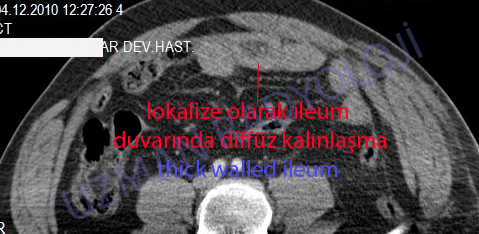

КТ ретроперитонеального фиброза: Изображения и диагностика